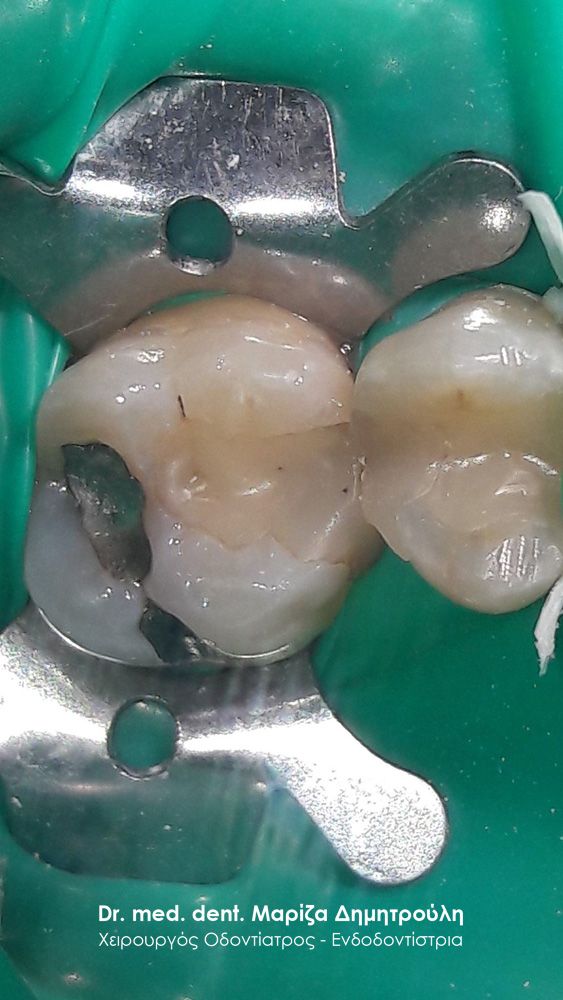

Περιστατικό – Αντικατάσταση σφραγισμάτων δοντιών

Ο ασθενής επιθυμούσε την αντικατάσταση των μαύρων σφραγισμάτων αμαλγάματος στον πρώτο δεξιό γομφίο και στο δεύτερο γομφίο με λευκά σφραγίσματα σύνθετης ρητίνης. Η θεραπεία πραγματοποιήθηκε με τη χρήση ελαστικού απομονωτήρα, όπως ορίζουν τα παγκόσμια πρωτόκολλα οδοντιατρικής για την αφαίρεση των μαύρων σφραγισμάτων. Όταν οι οδοντίατροι χρησιμοποιούν απομονωτήτρα κατά την αφαίρεση σφραγισμάτων αμαλγάματος, τότε ο ασθενής εισπνέει ελάχιστα και δεν καταπίνει τον υδράργυρο, που απελευθερώνεται κατά τη διαδικασία αυτή.

ΠΡΙΝ

META